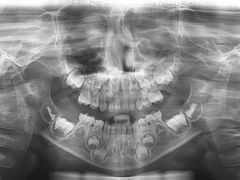

• 岳辰齿科(浦东长泰店)

• -岳辰齿科(浦东长泰店)